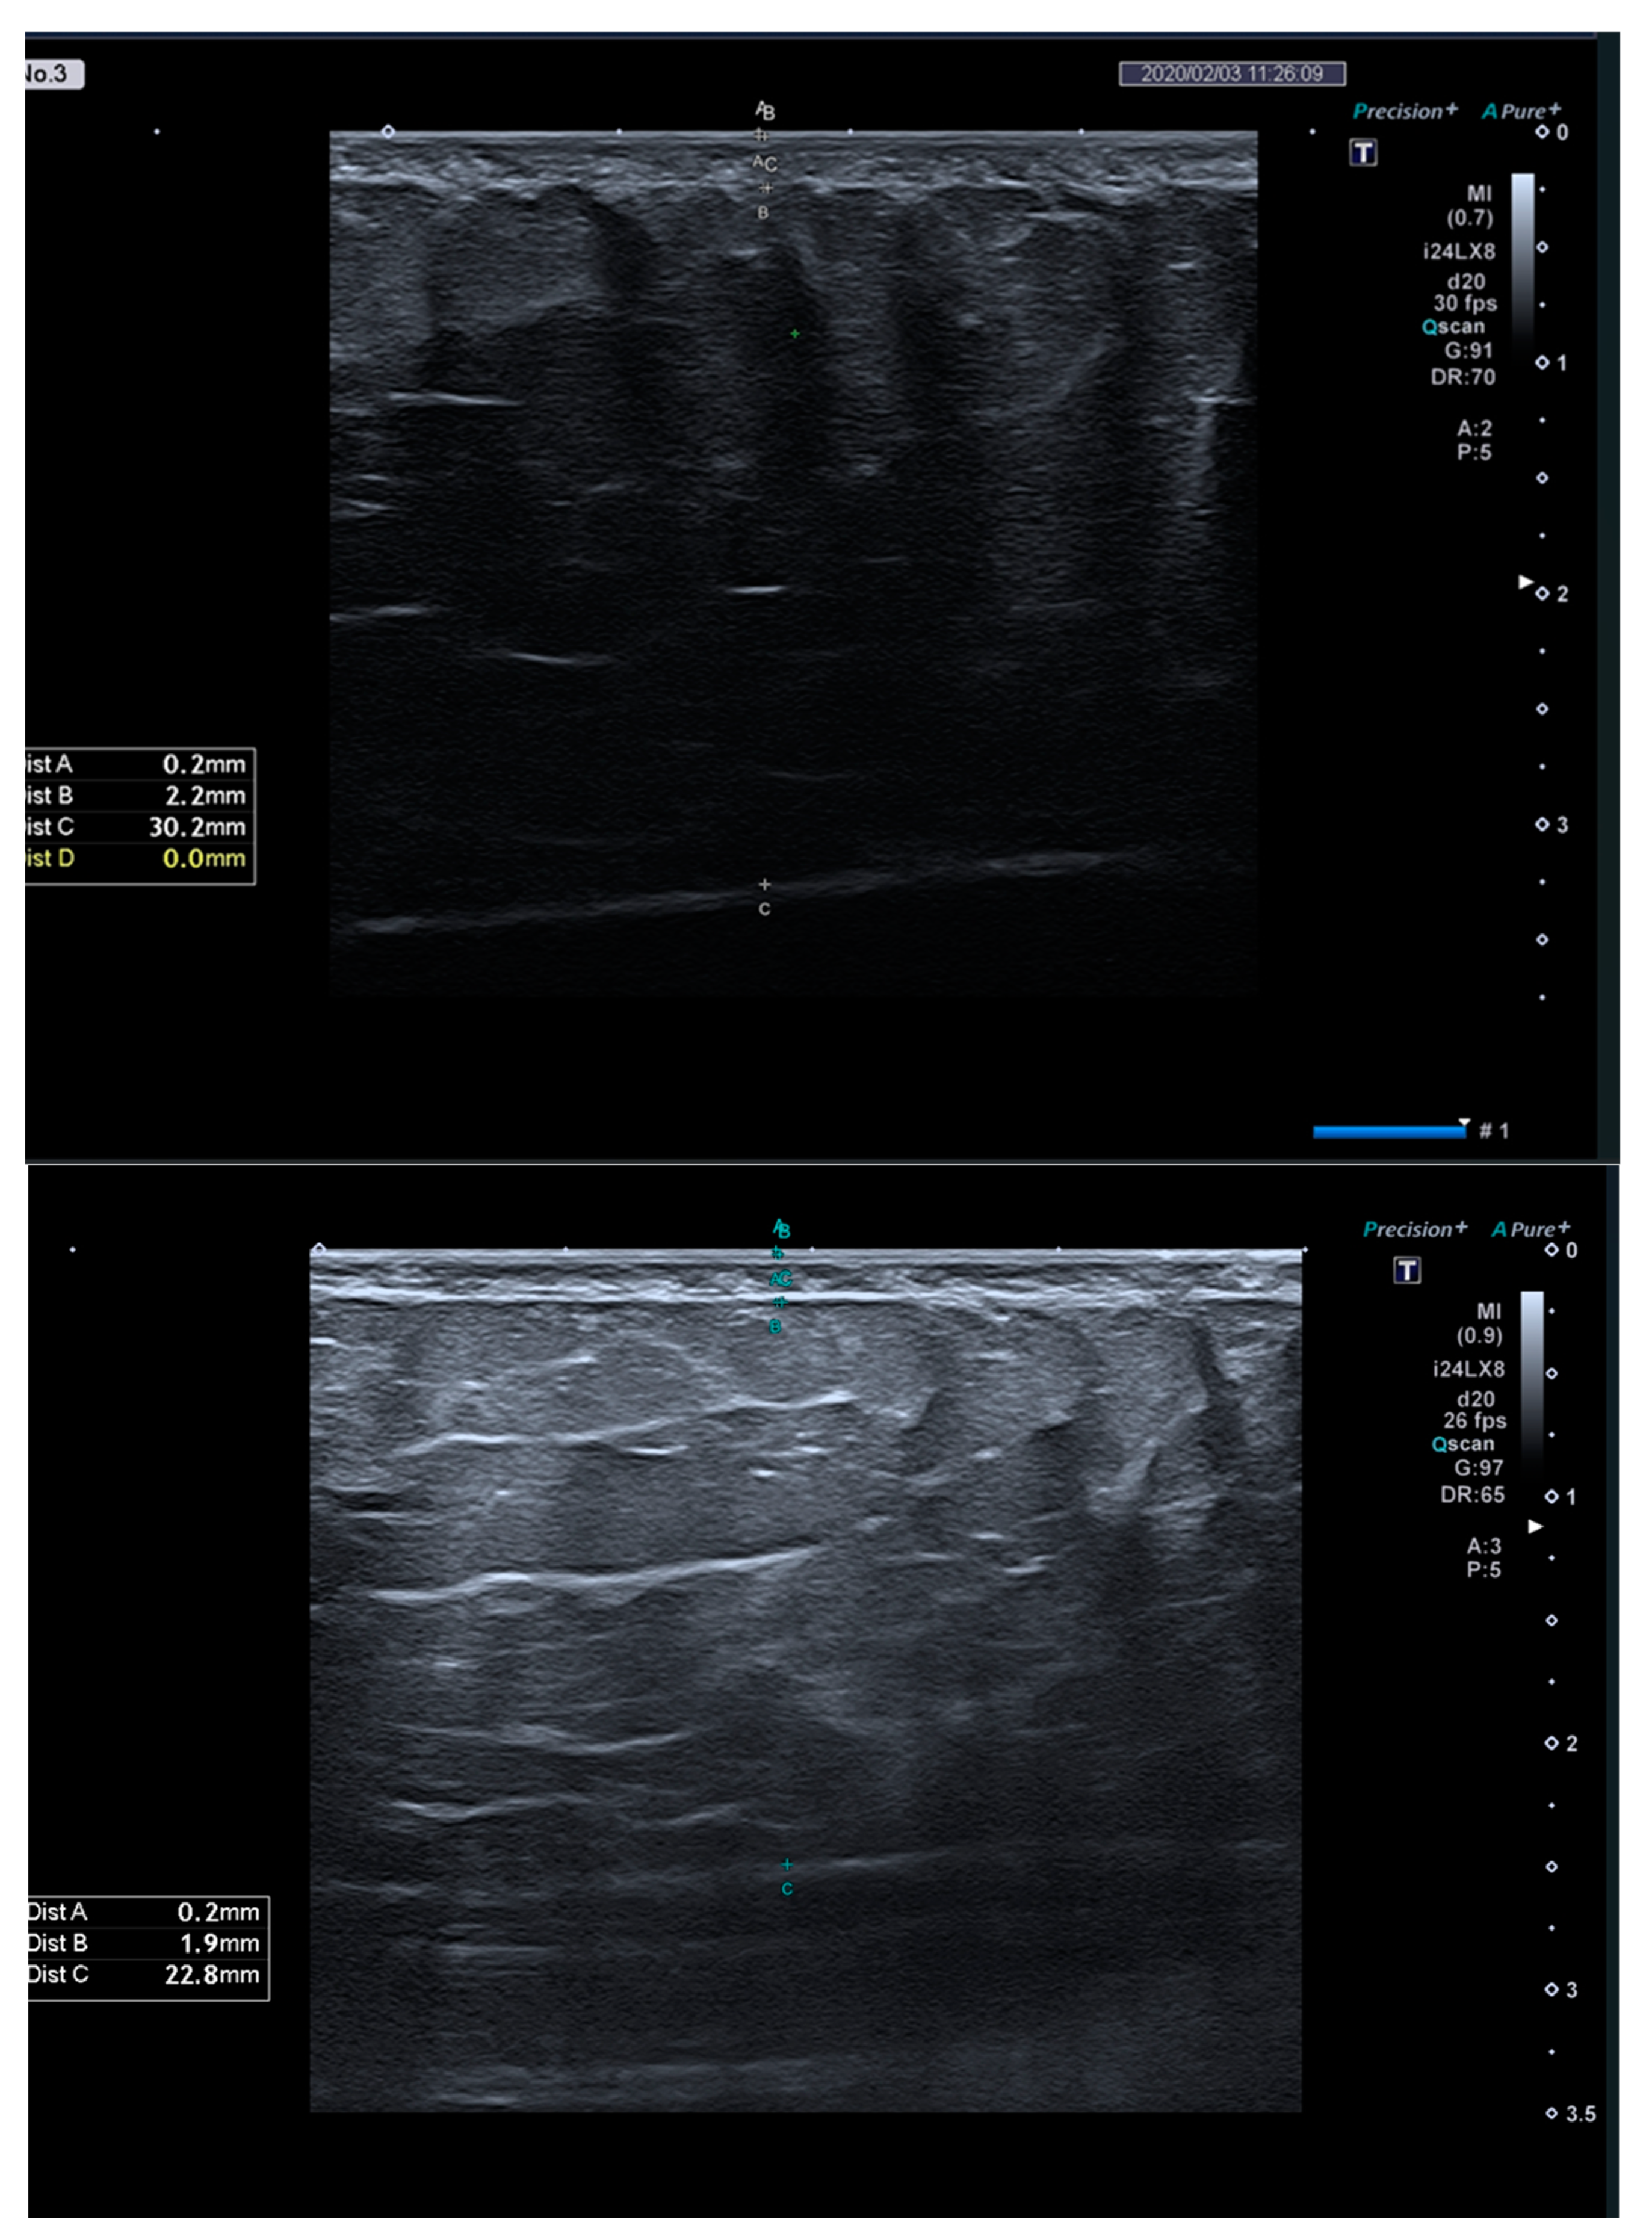

| SAT thickness, mm | ||||||

| M0 | 21.93 ± 6.66 | 17.42 ± 5.36 | 19.13 ± 10.30 | 0.410 | EG1: <0.001 | |

| M1 | 18.86 ± 7.01 | 14.29 ± 4.43 | 18.81 ± 10.07 | 0.282 | EG2: <0.001 | |

| M1-M0 (95% CI) | −3.07 ± 1.25 (−3.97; −2.17) | −3.13 ± 1.92 (−4.41; −1.84) | −0.32 ± 1.27 (−1.22; 0.59) | <0.001 a | 0.446 | CG: 0.449 |